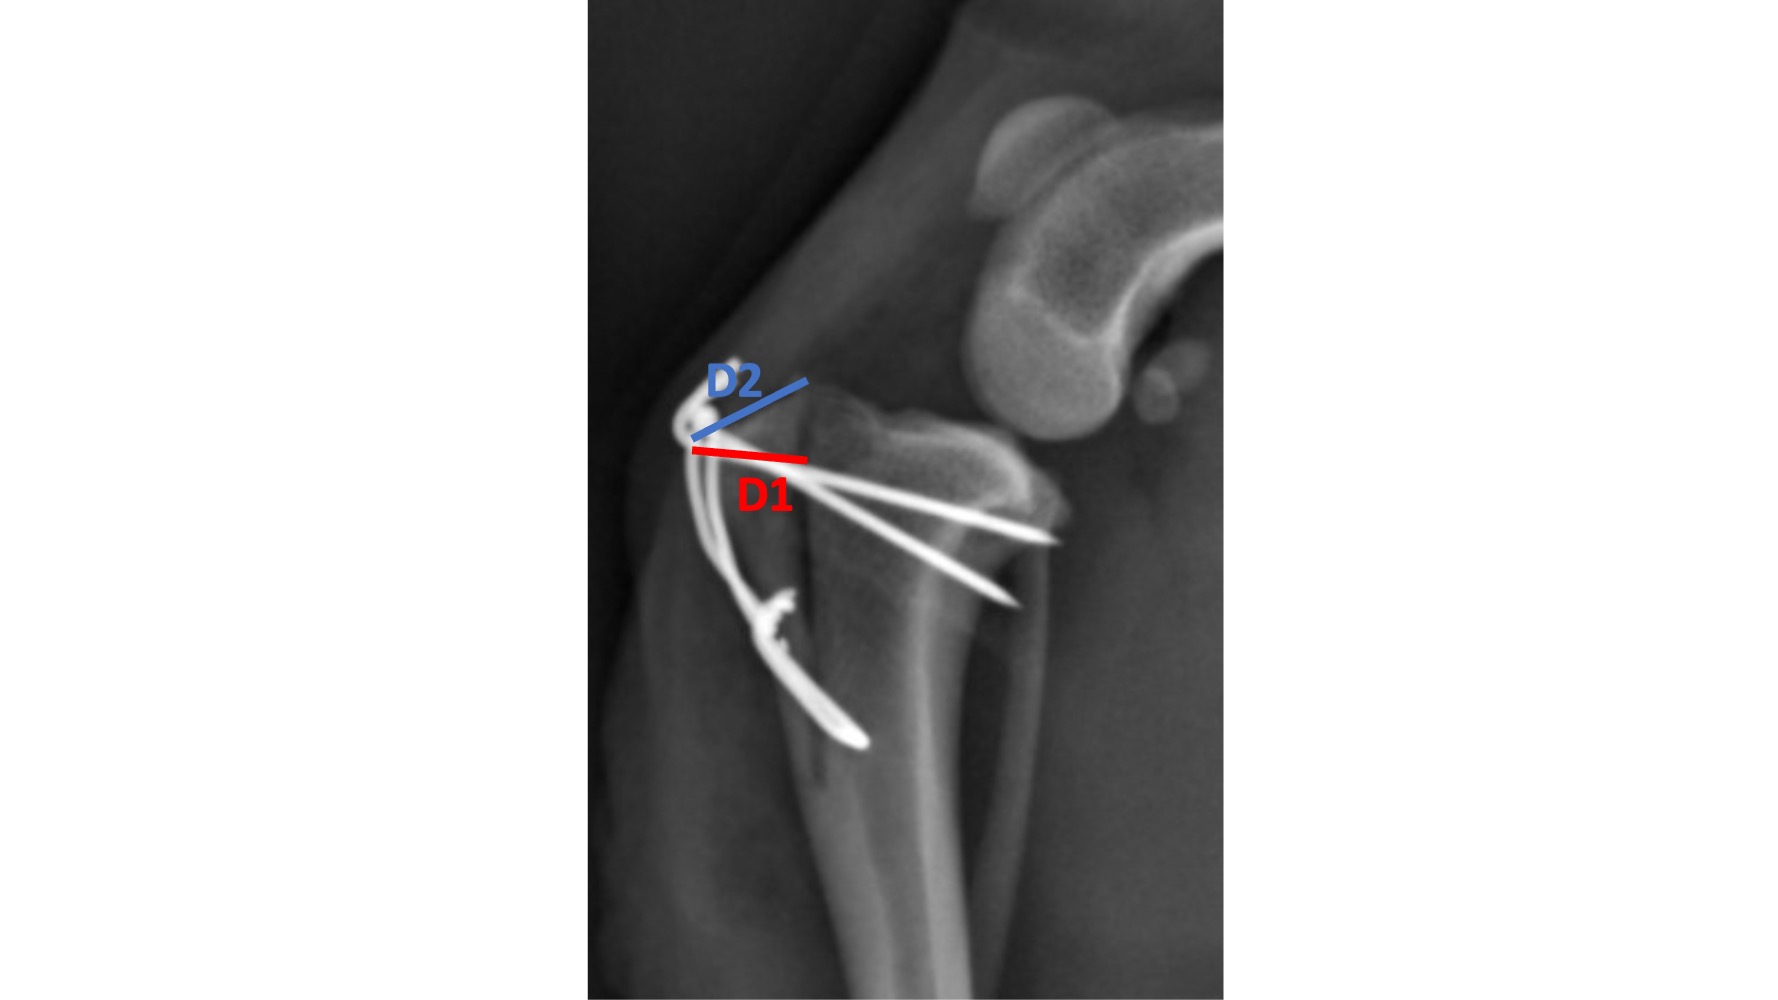

Tibial tuberosity osteotomy is often performed to treat patella luxation in dogs and to improve exposure for femoral osteotomy. Tibial tuberosity fracture occurs in up to 6% of cases. In patients undergoing tibial plateau leveling osteotomy (TPLO), there are measurement guidelines which reduce the risk of postoperative tibial tuberosity fracture. Our aim was to evaluate postoperative radiographs to identify whether these measurements, known as D1 and D2, can be used to plan tibial tuberosity osteotomies to reduce the risk of postoperative fracture.

267 dogs were identified, 50 dogs did not meet the inclusion criteria and were excluded giving a total of 217 dogs. Toy breeds were more likely to fracture than other breeds (p= 0.002). Pin position, size and number of pins did not affect the risk of tibial tuberosity fracture. A smaller (Log)D1 increased the risk of fracture (p=0.014). A D2 < 7mm had a sensitivity of 80% and specificity of80% for predicting dogs that will fracture.

Toy breeds should be considered at a higher risk of tibial tuberosity fracture than other breeds, and the smaller the size of the proximal tibia and tibial tuberosity segment, the greater risk. To reduce the risk of tibial tuberosity fracture, the value of D2 should be greater than, or equal to 7mm.